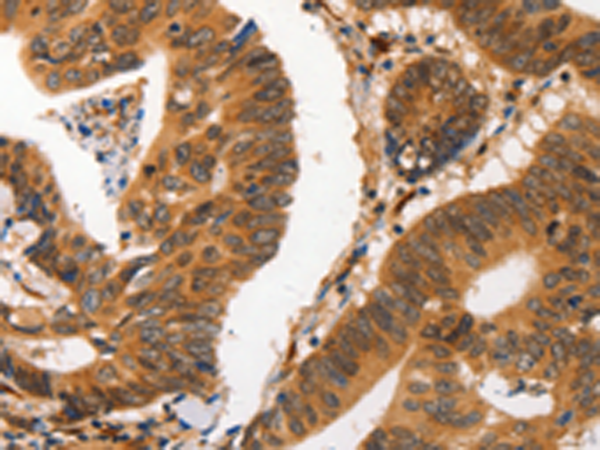

分类: 科研抗体货号: P00176别名: PAS3; MUC-15; PASIII应用: WB,IHC反应种属: Human, Mouse